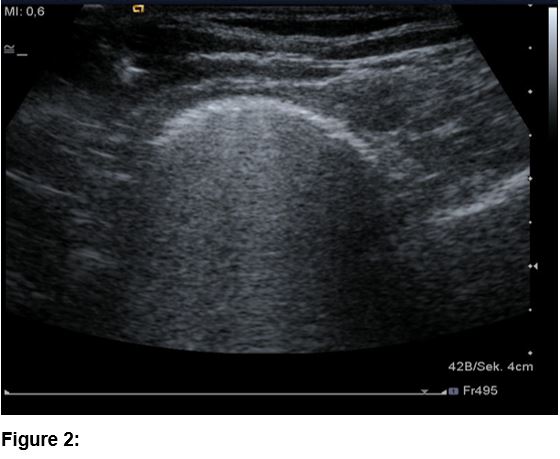

The clinical examination showed a patient in good general health condition with a BMI of 20 (kg/m2). The inspection of the throat and the oral cavity has not shown any pathologic findings. The most frequent triggers of dysphagia in the age group of 20-49 years [2,3] are due to mechanical obstruction (median neck cyst, nasopharyngeal carcinoma, disorders of the thyroid gland, etc.), autoimmune/inflammatory diseases (eosinophilic esophagitis, inflammatory myopathy, Sjögren’s syndrome, throat infection, etc.), esophageal dysmotility (achalasia, nutcracker esophagus, multiple sclerosis, etc.) and others (gastro esophageal reflux, anxiety disorder, heterotopic gastric mucosa, etc.).The first diagnostic procedure performed was an esophagogastroduodenoscopy with no major pathological findings, except for candida infection. The patient then proceeded to an esophageal passage with a barium swallow that showed an enlargement of the distal esophagus up to 3 cm (Figure 1). For various reasons no further diagnostic steps were performed with the diagnosis being made that this was psycho-functional. As the dysphagia was deteriorating, the patient attended our clinic to get an ultrasound examination of her neck which showed an impressive dilatation in the left lower neck area during the swallowing act, consistent with a dilatation of the lower esophagus (Figure 2, video-clip). This finding was confirmed by the subsequent esophageal manometry that was consistent with a congenital achalasia of type 2 according to the Chicago classification (figure 3).

Figure 2: Ultrasound (linear 9 MHz probe): during swallowing shows a 3 cm, sickle-shaped and hyperreflective structure consistent with a dilatation of the lower esophagus.